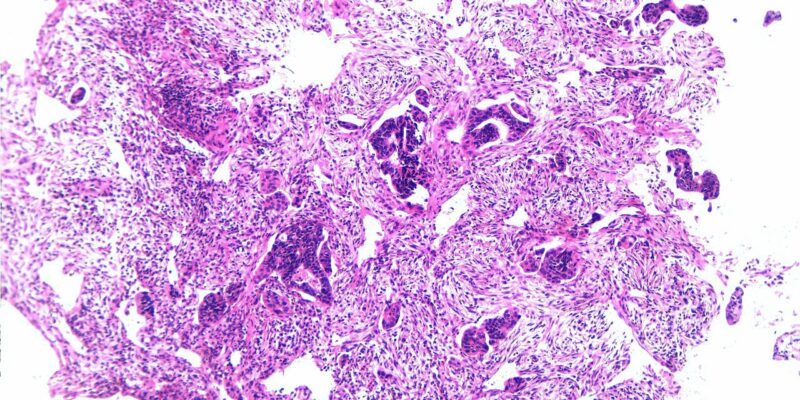

Rezecția polipilor colonici, denumită polipectomie, se realizează cel mai frecvent endoscopic, atunci când pacientul efectuează colonoscopia și sunt depistate aceste leziuni premaligne. În funcție de numărul, dimensiunea și rezultatul histopatologic ale polipilor rezecați sunt enunțate recomandările de monitorizare colonoscopică a...